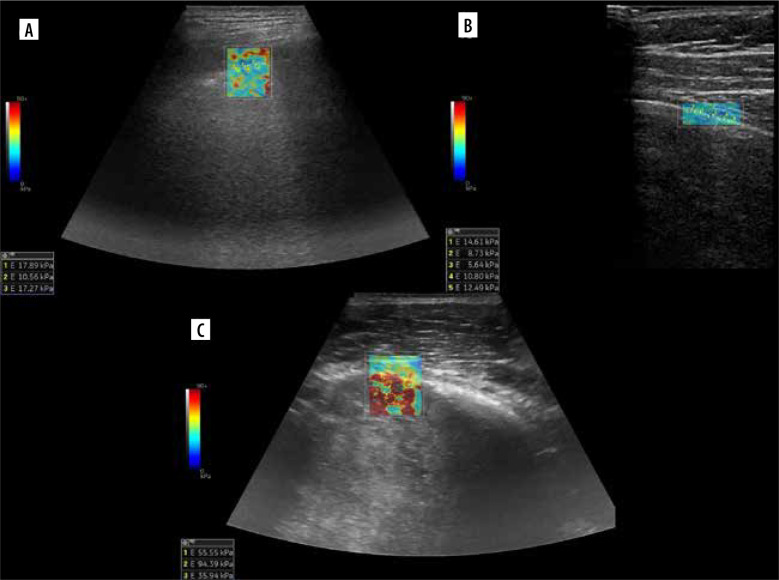

In recent years, lung ultrasound (LUS) has developed rapidly, and it is gaining growing popularity in various scenarios. There are constant attempts to introduce it to new fields. In addition, knowledge regarding lung and LUS has been augmented by the recent COVID-19 pandemics. In the first part of this review we discuss lines, signs and pheno-mena, profiles, some applications, and misconceptions. An aim of the second part of the review is mainly to discuss some advanced applications of LUS, including lung elastography, lung spectroscopy, colour and spectral Doppler, contrast-enhanced ultrasound of lung, speckled tracking of pleura, quantification of pulmonary oedema, predicting success of talc pleurodesis, asthma exacerbations, detecting chest wall invasion by tumours, lung biopsy, estimating pleural effusion volume, and predicting mechanical ventilatory weaning outcome. For this purpose, we reviewed literature concerning LUS.